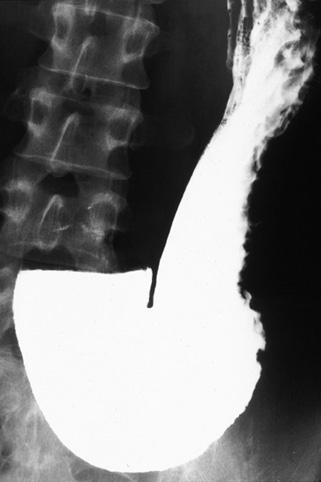

疾患(病理主体)の分類悪性上皮性腫瘍/印環細胞癌

部位(臓器別)胃(部位)/体部

検査方法X-P

腫瘍の肉眼分類0型(表在型)/IIc型(IIc)

病変の最大径(ミリ)30〜34

腫瘍の深達度m